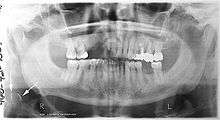

A dental panoramic radiograph, showing the maxilla and mandible, all the teeth including the "wisdom teeth," the frontal and maxillary sinuses, the nasal cavity and the temporomandibular joint and other near by head and neck anatomy. | |

A panoramic radiograph is a panoramic scanning dental X-ray of the upper and lower jaw. It shows a two-dimensional view of a half-circle from ear to ear. Panoramic radiography is a form of tomography; thus, images of multiple planes are taken to make up the composite panoramic image, where the maxilla and mandible are in the focal trough and the structures that are superficial and deep to the trough are blurred.